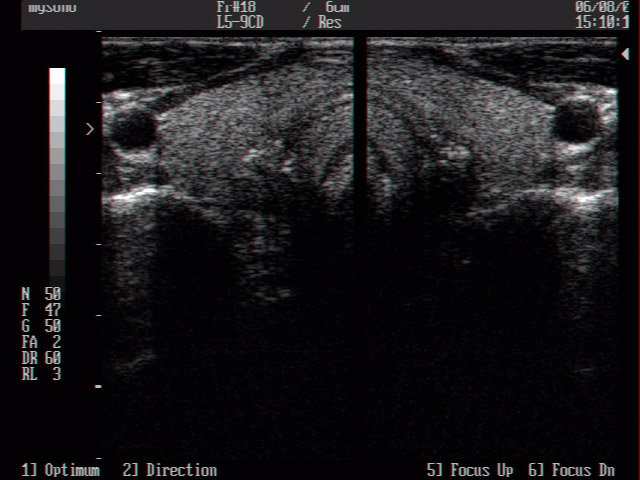

Thyroid, B-mode (echogramm №16)

Echogramm was received by ultrasound scanner MySono-201 (out of production).